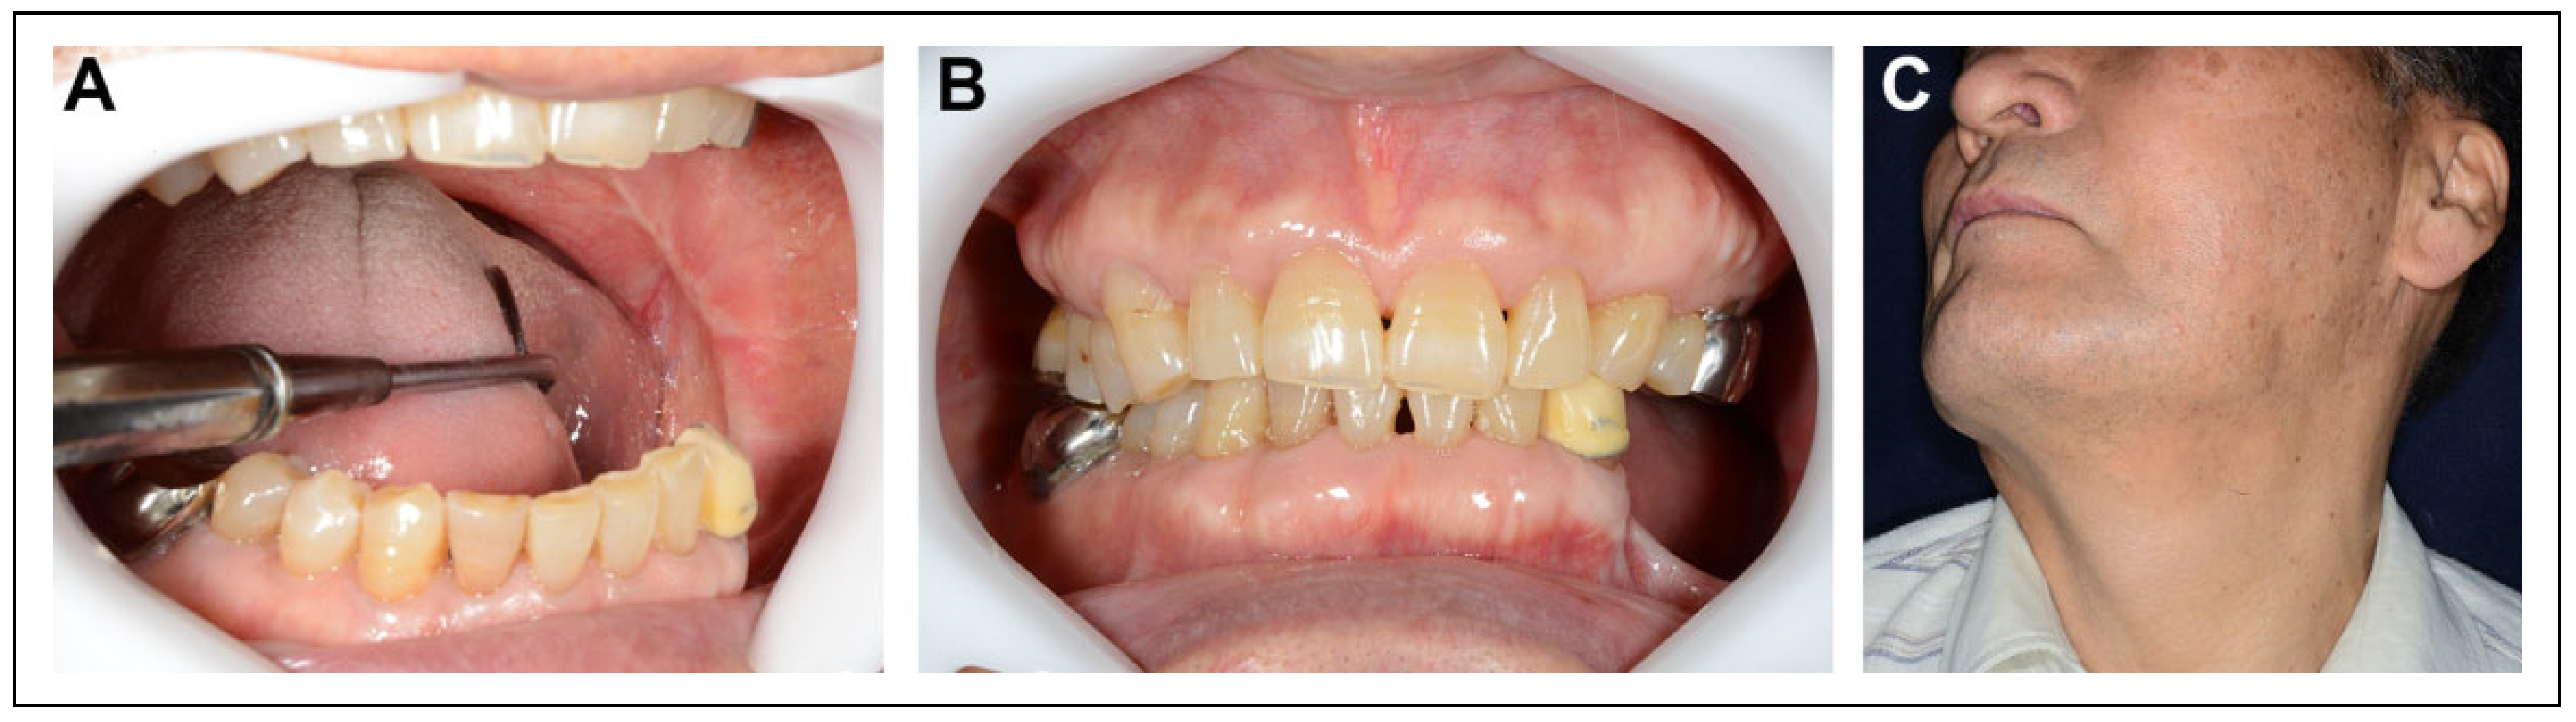

Case Presentation

Postoperative Course